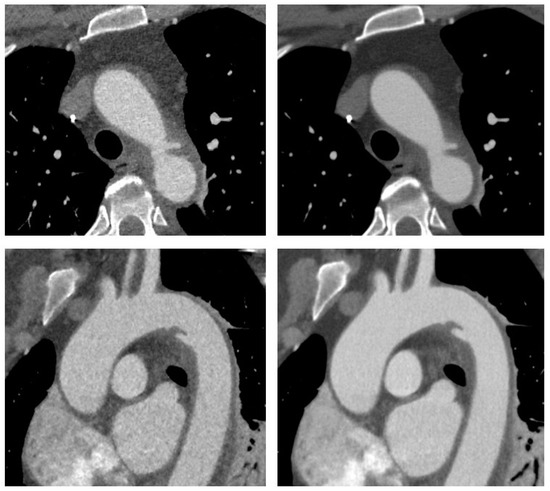

| Obese Patients (n = 17) | Normal-Weight Patients (n = 17) | |||||

|---|---|---|---|---|---|---|

| Contrast-to-Noise-Ratio | ASIR-V | DLIR | p-Value | ASIR-V | DLIR | p-Value |

| Ascending Aorta | 7 (6–8) | 14 (12–16) | <0.0001 | 8 (8–9) | 19 (15–22) | <0.0001 |

| Thoracic descending aorta | 7 (6–7) | 13 (11–15) | <0.0001 | 8 (7–9) | 18 (13–19) | <0.0001 |

| Abdominal aorta | 12 (8–13) | 19 (15–24) | <0.0001 | 9 (7–12) | 16 (11–21) | <0.0001 |

| Iliac arteries | 14 (12–15) | 21 (19–25) | <0.0001 | 15 (13–16) | 24 (19–28) | 0.001 |

| ASIR-V | DLIR | p-Value | |

|---|---|---|---|

| Reader 1 | |||

| Ascending aorta | 4 (4–5) | 5 (5–5) | <0.0001 |

| Thoracic descending aorta | 4 (4–5) | 5 (5–5) | <0.0001 |

| Abdominal aorta | 4 (4–4) | 5 (4–5) | <0.0001 |

| Iliac arteries | 5 (4–5) | 5 (5–5) | <0.0001 |

| Reader 2 | |||

| Ascending Aorta | 4 (4–4) | 5 (4–5) | <0.0001 |

| Thoracic descending aorta | 4 (4–4) | 5 (5–5) | <0.0001 |

| Abdominal aorta | 4 (3–4) | 5 (4–5) | <0.0001 |

| Iliac arteries | 4 (4–5) | 5 (5–5) | <0.0001 |